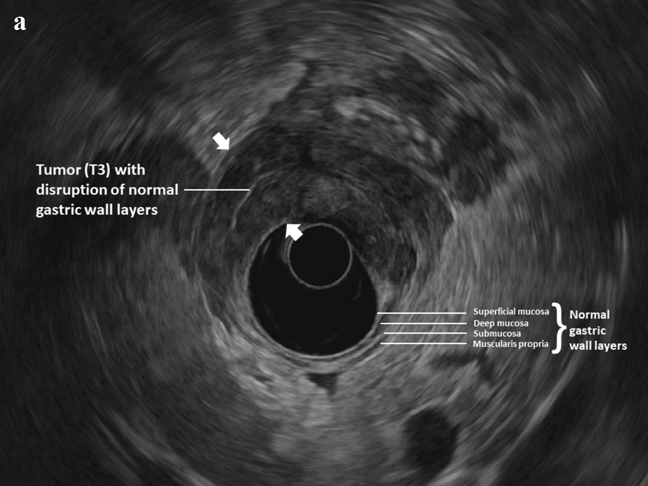

Endoscopic Ultrasound Predicts Risk of Occult Intra-Abdominal Metastases in Localized Gastric Cancer: A Validation StudyIn gastric cancer (GC) patients without imaging evidence of distant metastasis, diagnostic staging laparoscopy (DSL) is recommended to detect radiographically occult peritoneal metastasis (M1). DSL carries a risk for morbidity and its cost-effectiveness is unclear.